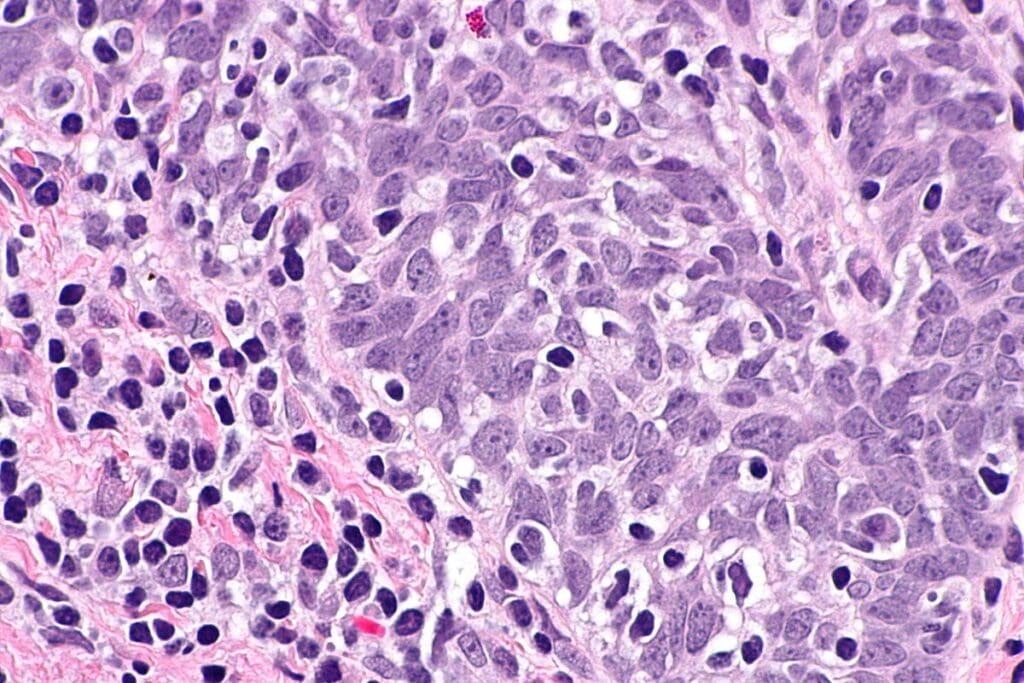

Glioblastoma: Arising from Glial Cells in the Brain

Glioblastoma, by contrast, comes from glial cells in the brain. Glial cells help neurons by giving them oxygen and nutrients and cleaning up dead cells. Glioblastoma grows quickly, forming aggressive tumours.

The glial cells that lead to glioblastoma are vital for neuron health. When they turn cancerous, they create very dangerous tumors.